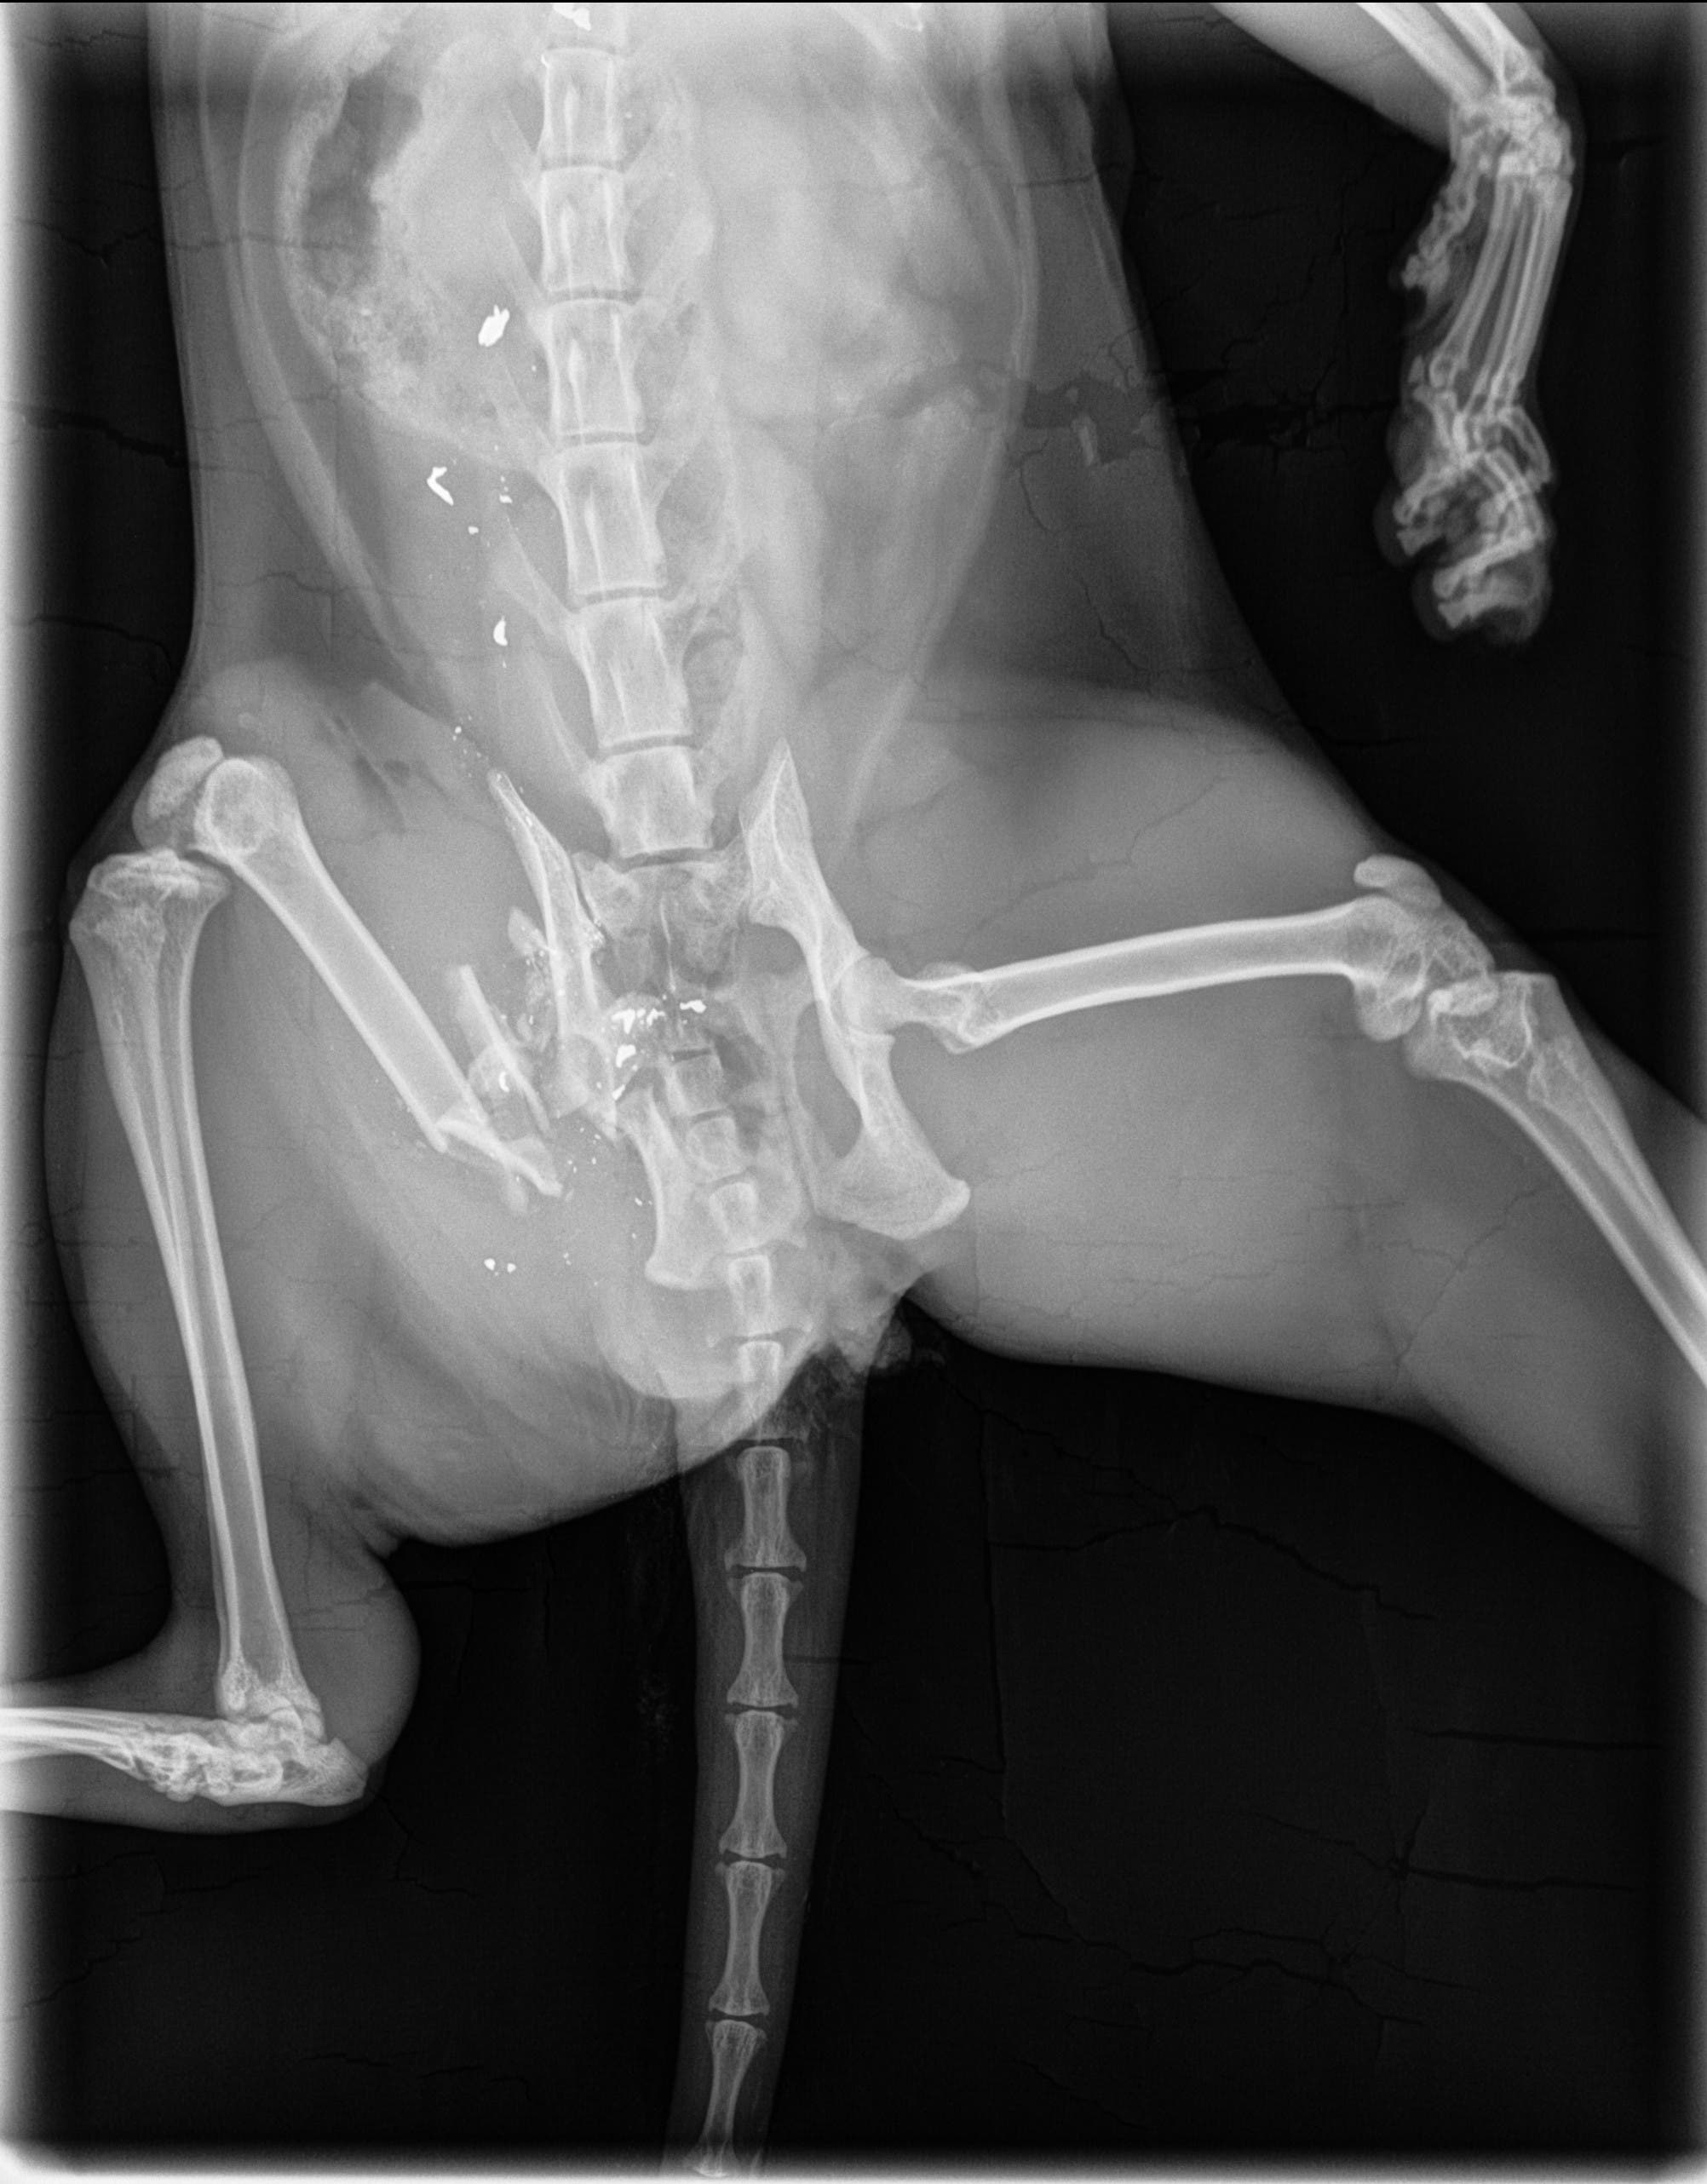

The domestic 7-year-old black cat named Simon was shot by a high powered pellet or a small caliber bullet, they said.

Simon was let outside July 2. On July 4 he returned home with an injury to his hind quarters.

The owner took the cat to the Brewster Veterinary Hospital, and the vet found metal fragments throughout the midsection. The projectile caused a broken femur bone and pelvis.

The veterinary surgeon was able to remove a small fragment of the projectile, but the rest had to be left in so as not to further endanger the cat’s life. SPCA officials said the shooting caused extreme pain, serious physical injury and permanent physical impairment of Simon’s hind legs.